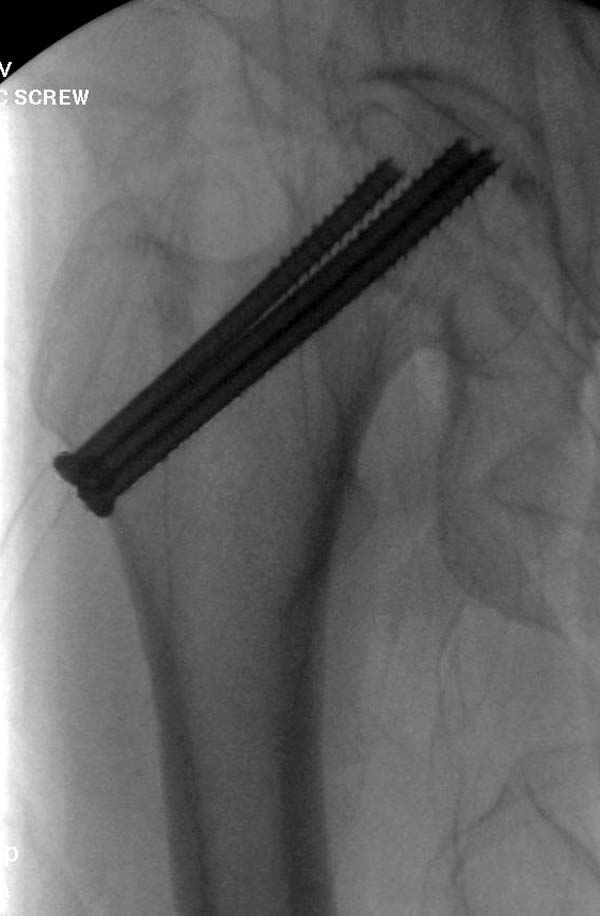

Наверное речь идет насчет parallel guide из набора. Применяем по возможности всегда, но,

как видно на снимке, не всегда получается

паралельно.

Такие несмещенные переломы обычно для молодых резидентов, и бывают технические неточности, но в этом случае посчитали фиксацию адекватной.